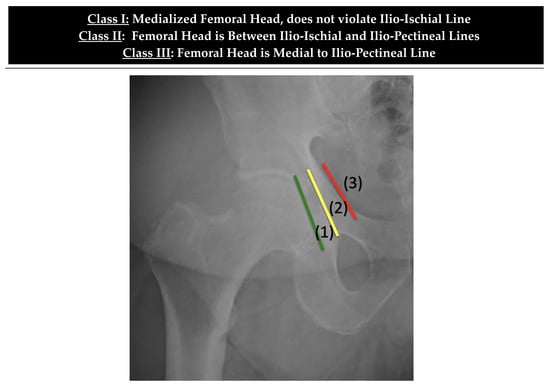

| Class | Ilioischial Line | Iliopectineal Line | Recommended Treatment |

|---|---|---|---|

| I | Intact (femoral head medialized) | Intact | Implant Placement: Lateralization of acetabular component to match native rim. Standard component needed, no need for screw augmentation. Bone graft: Not likely required. |

| II | Violated | Intact | Implant Placement: Lateralization of acetabular component to rim, consider use of larger or jumbo component. Screw fixation optional. Consider lateralized acetabular liner. Bone Graft: Likely required medially with impaction grafting. |

| III | Violated | Violated | Implant Placement: Lateralization of acetabular component, consider use of jumbo, deep profile, revision, or multi-hole component. Screw fixation is strongly recommended in multiple planes to augment construct stability. Consider lateralized acetabular liner. Bone Graft: Universally required. Autograft reamings and morselized cortical bone from native head is recommended, consider use of additional allograft bone to fill large defects. Powdered antibiotic can be added to graft mixture to reduce risk of prosthetic joint infection. |